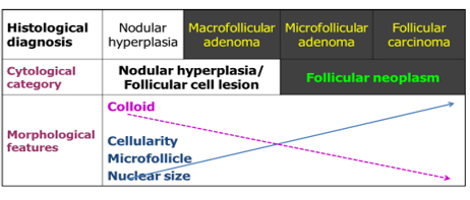

Ans : Adenoma thyroid.

The close differentials at cytology are thyroid adenoma and follicular hyperplasia in a goiter.

Two categories of follicular lesions are seen at FNA. 1. Follicular lesion (atypia) of undetermined significance - to be managed by repeat FNA 2. Follicular neoplasm (follicular or Hurthle cell neoplasm - to be managed most likely by surgical excision).

Diagrammatic rationale for cytologic diagnosis of follicular neoplasm.